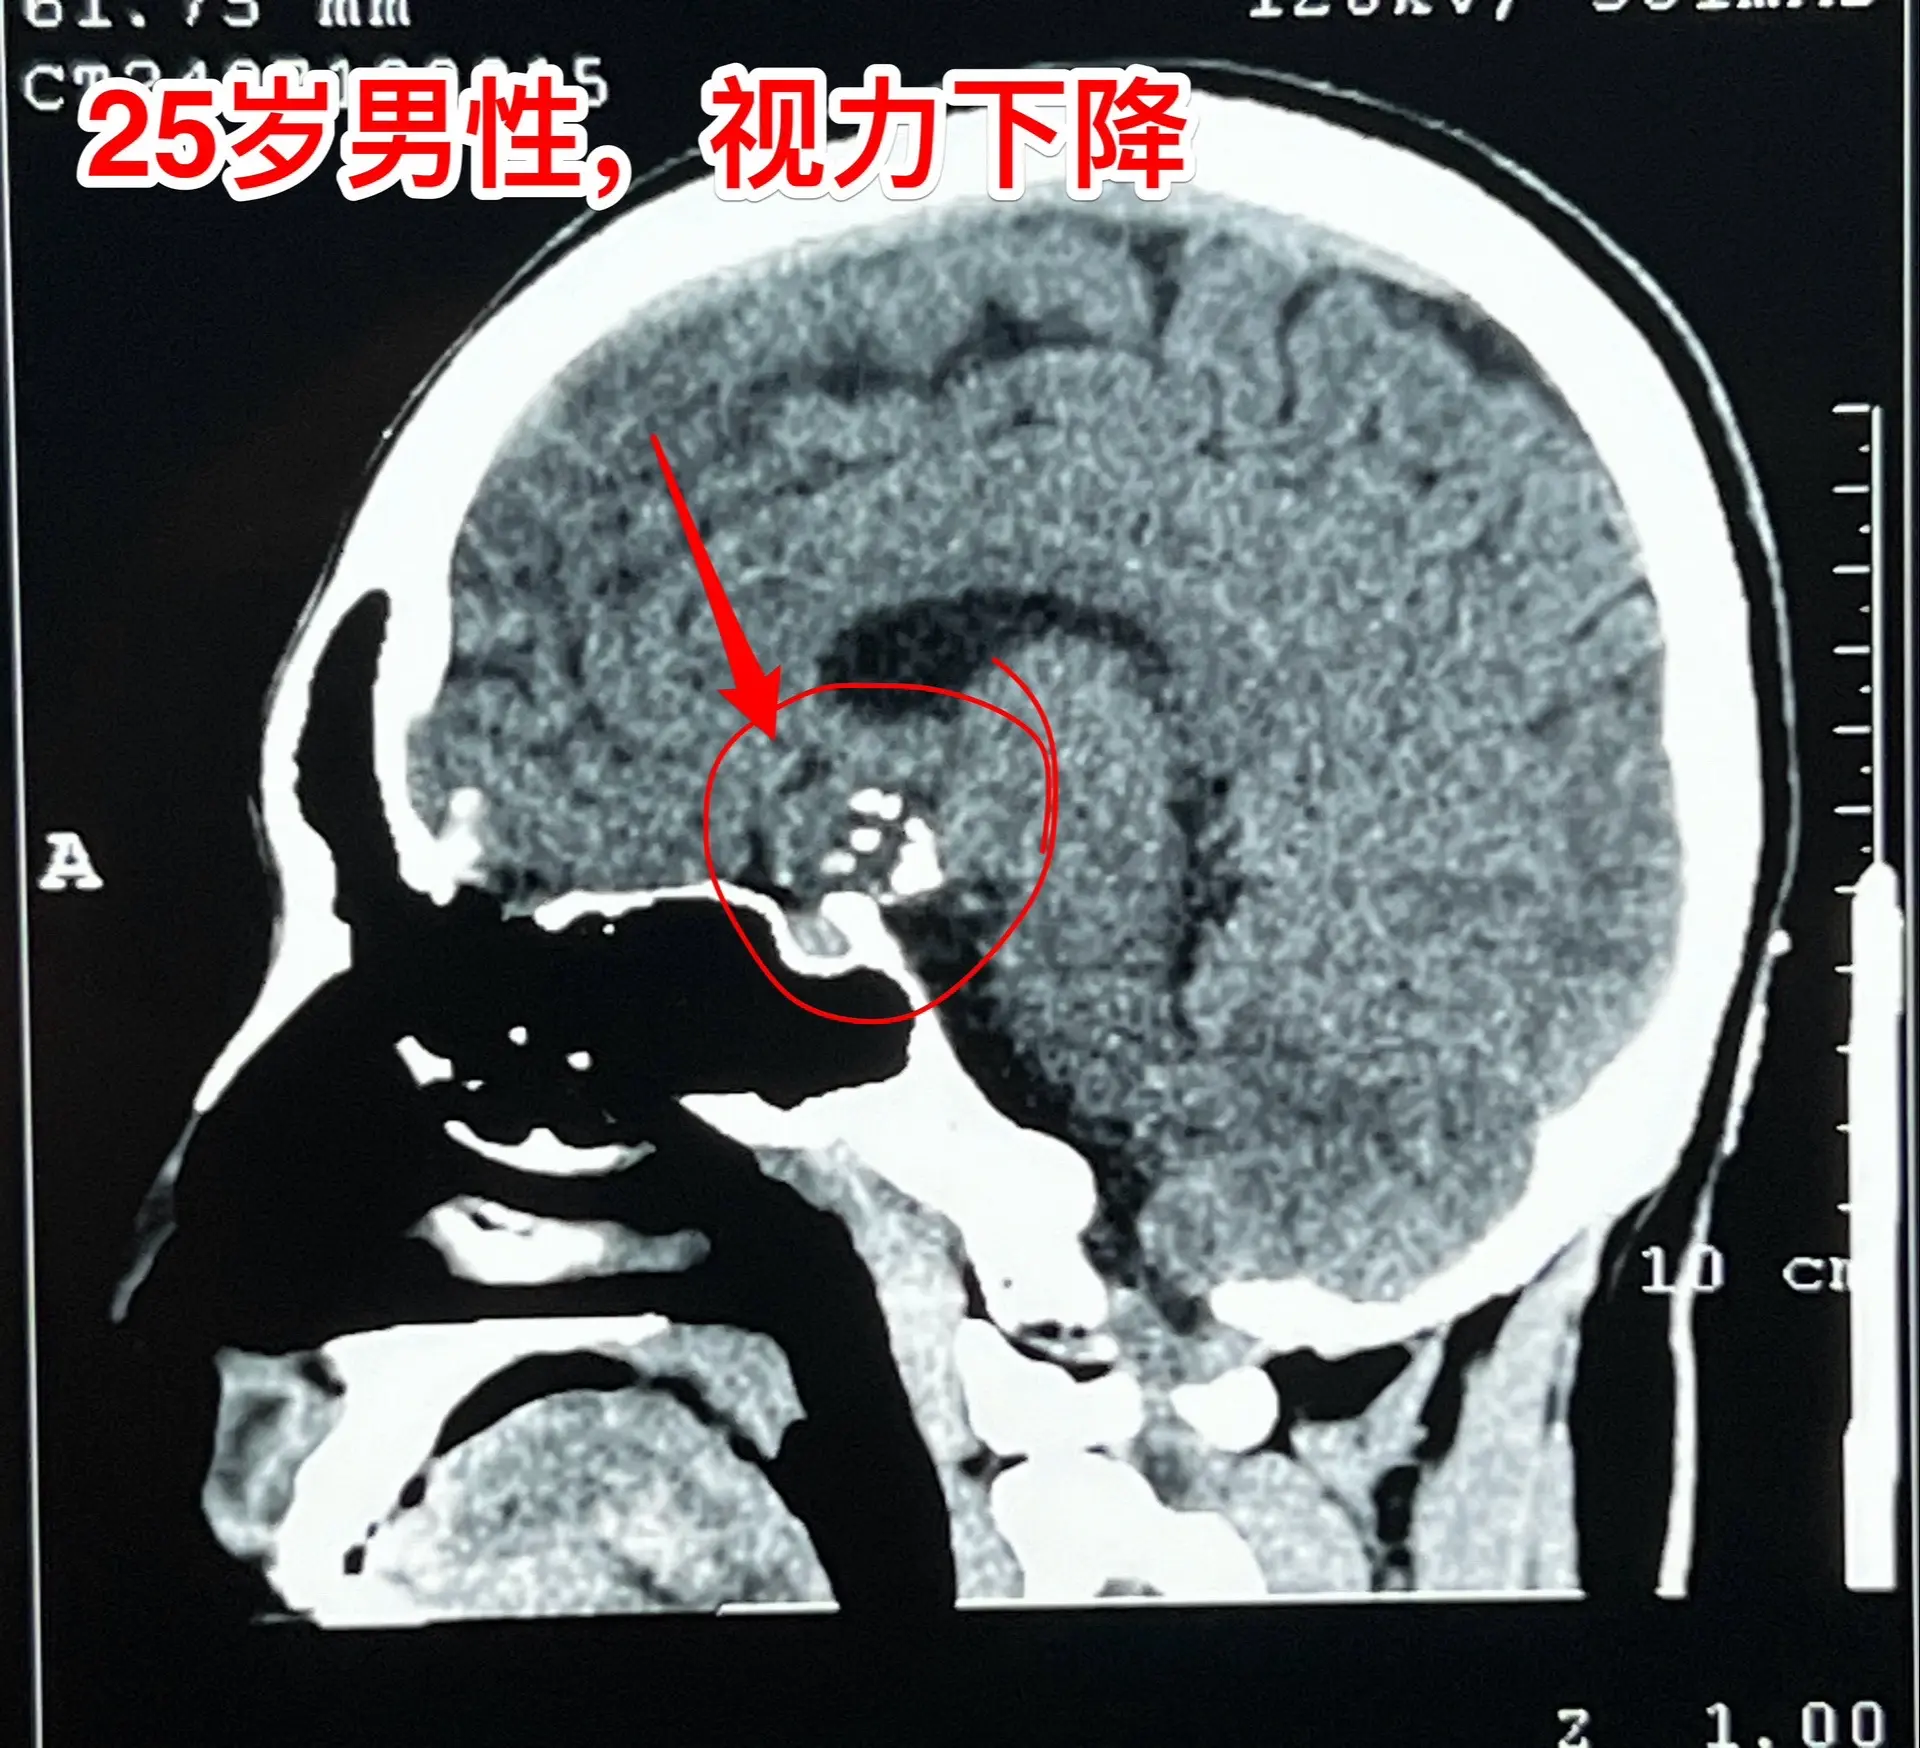

一天两台颅咽管瘤手术对于我们科是常态!7月24日我们科按常规安排了两台颅咽管瘤:第一个5岁男孩子,广东人,因为身高增长缓慢发现了颅咽管瘤。第二个是25岁的三门峡市男性,因为视力下降发现了颅咽管瘤。两个手术都顺利完成。 这样的手术安排对于我们三博脑科医院神经外科八病区来说几乎是常态。有时候一天完成两台复发颅咽管瘤手术,最多的时候一天完成三台颅咽管瘤手术。应该说如果一天只作一个颅咽管瘤手术是比较合理的,一天作两个劳动强度是很高的,不值得提倡。